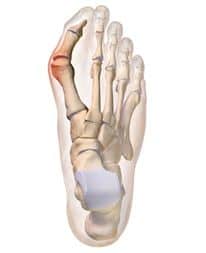

ΠΑΘΗΣΕΙΣ ΠΟΔΟΚΝΗΜΙΚΗΣ & ΑΚΡΟΥ ΠΟΔΟΣ

Διαβάστε περισσότερα για τις παθήσεις ποδοκνημικής και άκρου ποδός